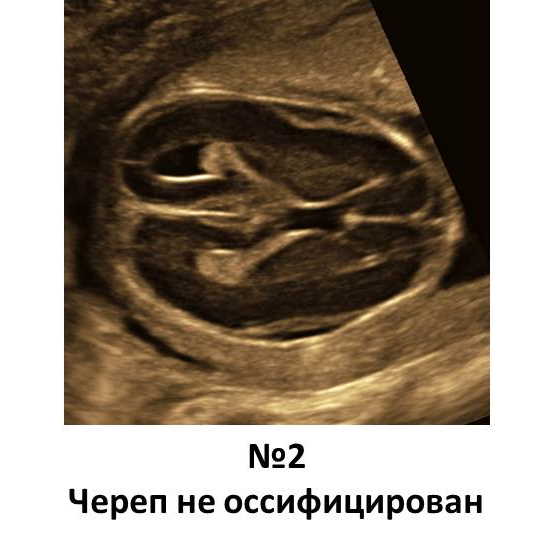

• ​На снимке №2 оссификация черепа отсутствует. Обращаем внимание, как хорошо видны структуры мозга, равномерно на всем протяжении. Это признак патологии- системной скелетной дисплазии. Чаще- несовершенного остеогенеза. Также может быть при гипофосфатазии. Окончательный диагноз- по специфическому исследованию плодного материала. Прогноз в обоих случаях- неблагоприятный.